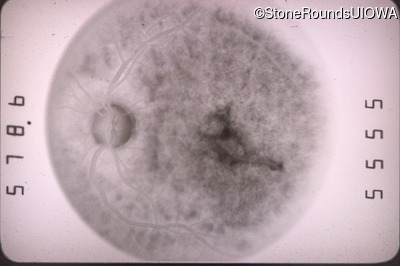

Fluorescein Angiography - Right - 20/100 -1

Exemplar